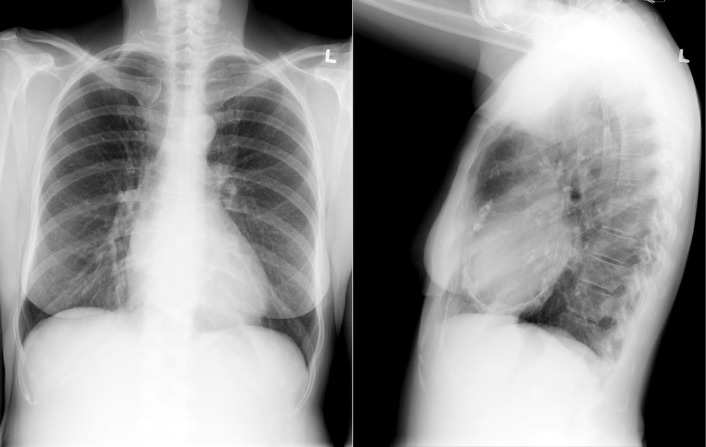

Pericardial Calcification

Pericardial calcification ( Figs. 27-1 to 27-4 ) is most prominent in the interventricular and atrioventricular grooves, and lateral to the right atrial and ventricular walls ( Graphic 27-1 ). When looking for pericardial calcification, it is necessary to scrutinize the lateral chest radiograph well, particularly the diaphragmatic surface. Pericardial calcification does not usually involve the left heart as much the right heart, and it does not often involve the apex (which, if calcified, is far more often due to prior infarction). Pericardial calcification should prompt serious consideration of the diagnosis of constrictive pericarditis, and clinicians should seek other radiographic and clinical features of constriction.